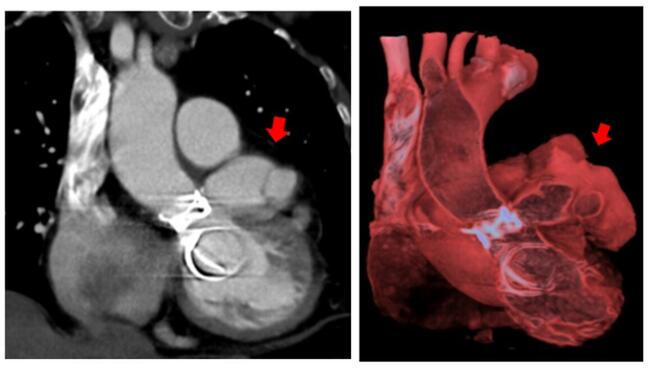

A 65-year-old woman underwent aortic and mitral valve replacement with a mechanical prosthesis due to rheumatic valve disease in 2019. Preoperative coronary angiography showed no coronary lesions (Figure 1). The echocardiogram showed a preserved left ventricular ejection fraction.

In 2022, she was admitted to the hospital for NSTEMI. Coronary angiography was performed (Figure 2) with the following findings:

- Left main coronary artery without significant stenosis.

- Left anterior descending artery (LAD) with proximal systolic compression phenomenon without complete collapse. Remaining vessel without lesions.

- Circumflex artery (Cx) with complete systolic compression phenomenon.

- Dominant right coronary artery without significant lesions.